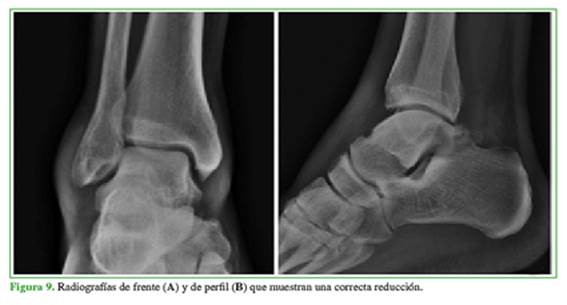

Se realizó la reducción cerrada de urgencia, bajo anestesia en el quirófano (Figura 9). Se lo inmovilizó con un yeso que se mantuvo durante cuatro semanas, luego usó una bota walker por dos semanas más y cumplió el protocolo de rehabilitación. Se autorizó la carga parcial desde la semana 6 y la carga total, a partir del tercer mes. El paciente interrumpió su seguimiento y consultó nuevamente luego de dos años de la cirugía, por lo cual no cumplió con el control anual estipulado. En el seguimiento alejado, el puntaje en la escala analógica visual fue de 0/10, no sentía molestias al practicar actividades deportivas. En el examen físico, se constató un rango de movilidad completo comparado con el contralateral y un puntaje de la AOFAS de 100 (máximo 100).